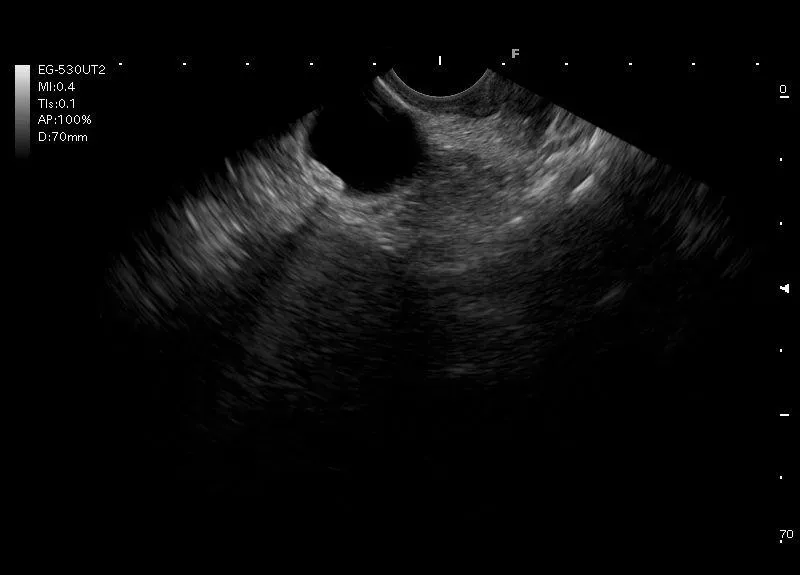

Drobne, kilkumilimetrowe, hiperechogeniczne struktury z niewielkim cieniem akustycznym, przemieszczające się podczas próby wstrząsania - mikrozłogi w pęcherzyku żółciowym